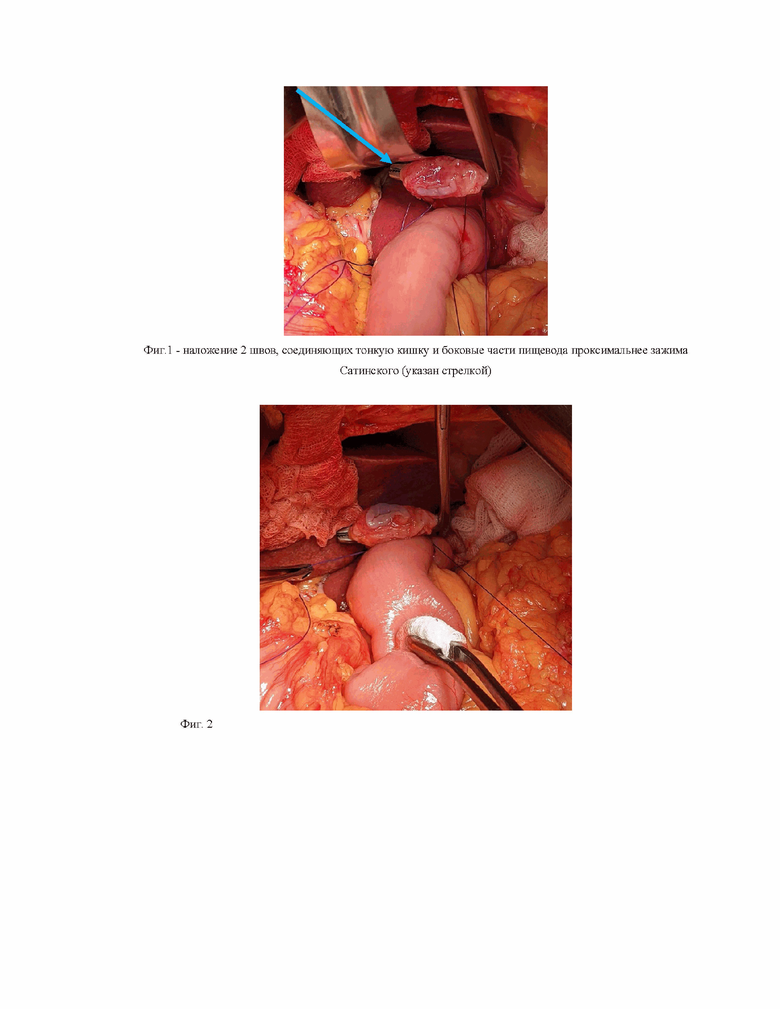

На расстоянии 2-3 см заглушенной части тонкой кишки накладываются 2 шва, соединяющие тонкую кишку и боковые части пищевода проксимальнее зажима Сатинского (фиг.1). После затягивания нитей (фиг. 2).